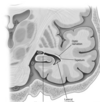

Key gyri on medial view of frontal lobe

Superior frontal gyrus

Paracentral lobule

Cingulate gyrus

Key sulci on medial surface of frontal lobe

Cingulate sulcus